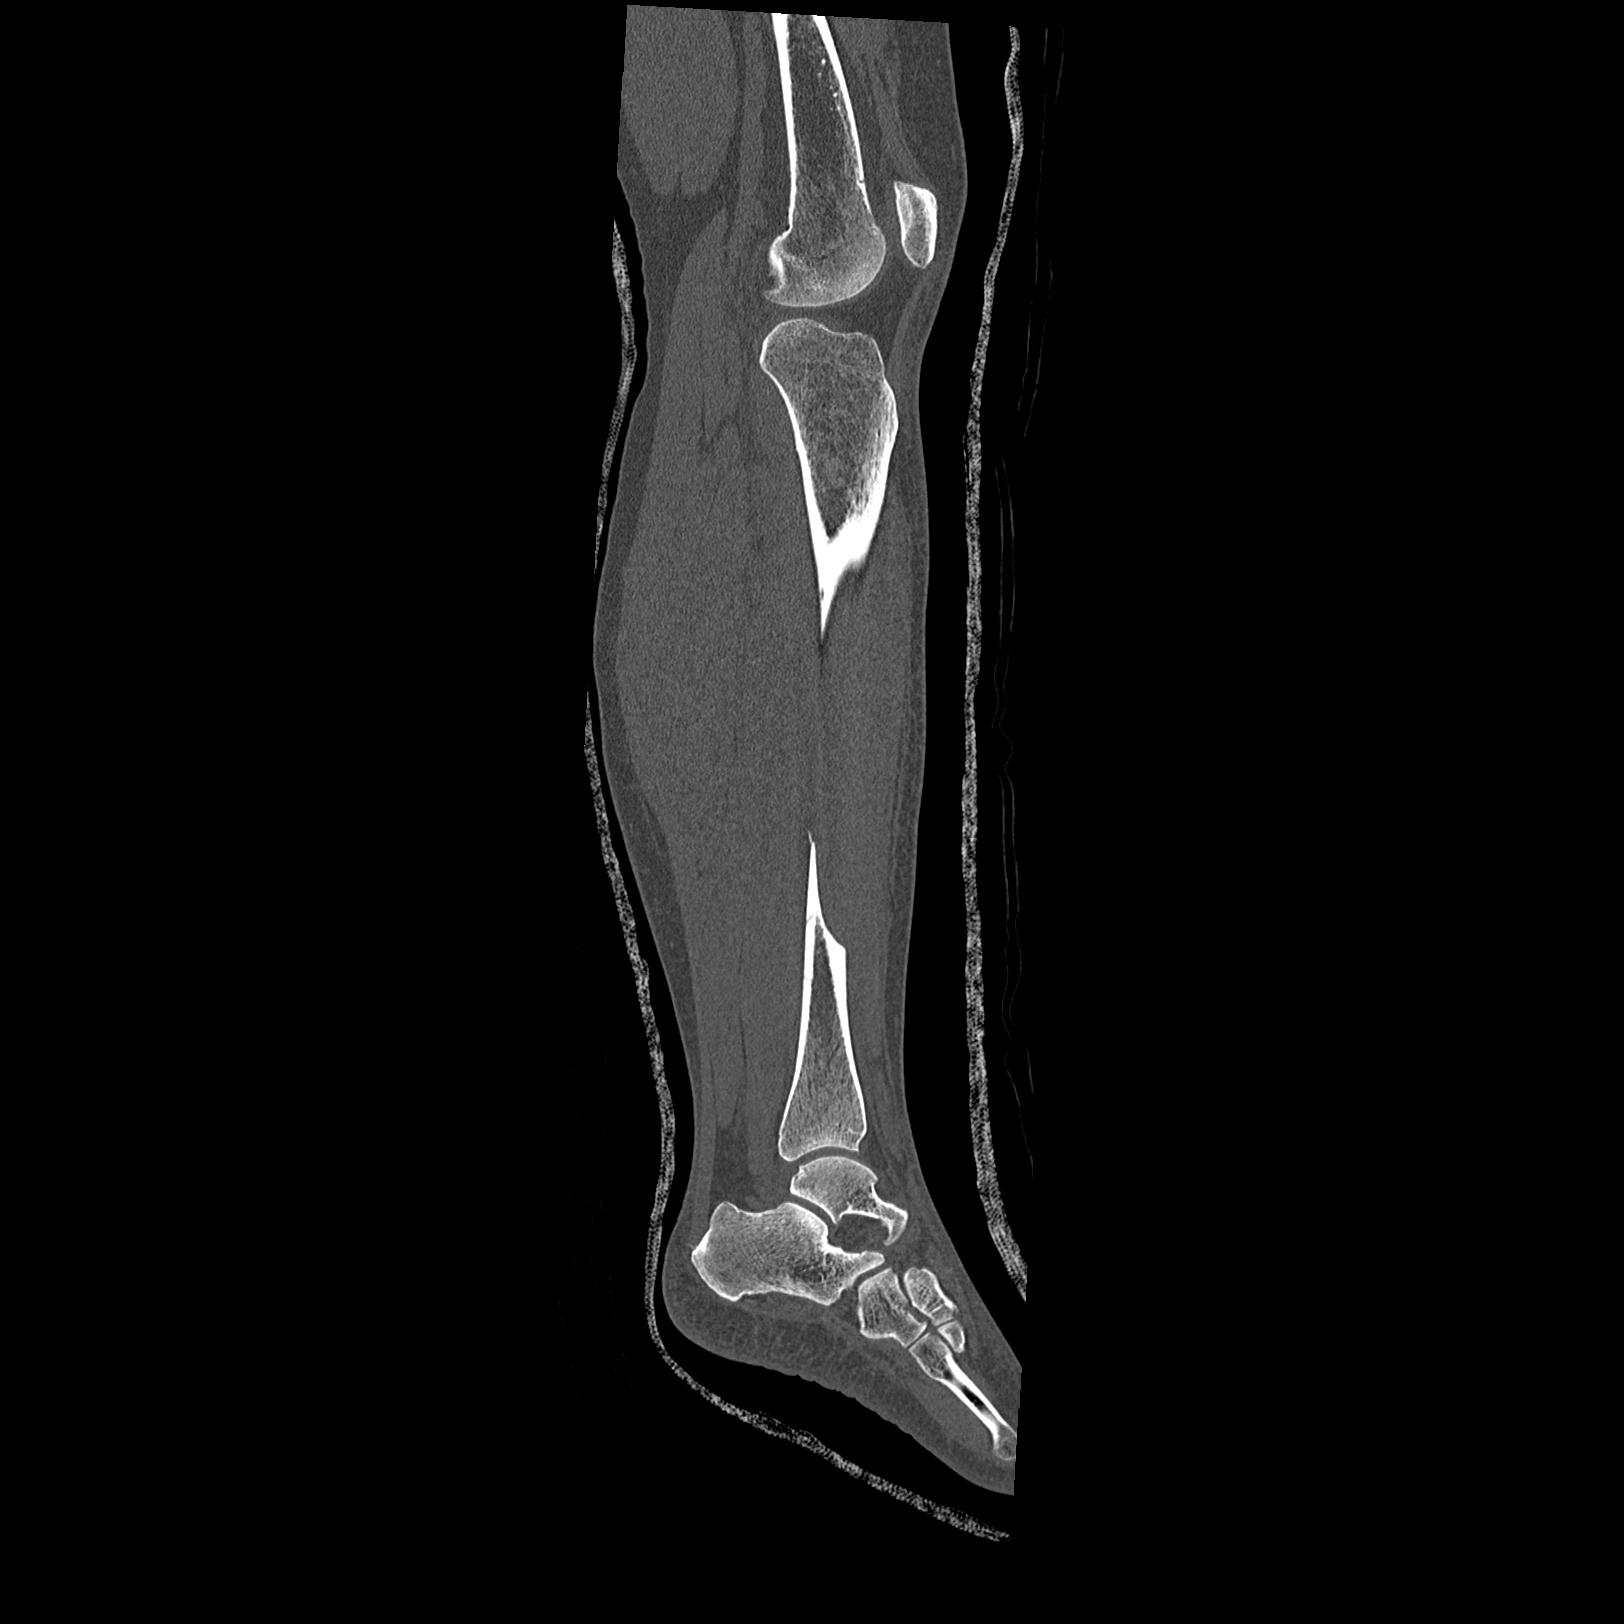

102803 1/12(キウスなし) 1/27 左下腿 4R 30歳女性 左脛骨軸内釘

102755 1/4 2R 1/15 2R 右足関節 68歳女性 右三果脱臼骨折

110211 1/6 1/8 左前腕 4R 15歳男性 橈骨骨幹部骨折